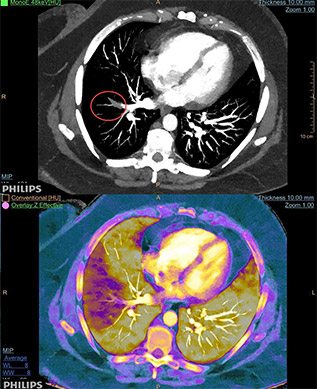

• Le mode mono énergie ou les cartes MonoE virtuelles (en unités Hounsfield) simulent un faisceau à RX monochromatique de 40 à 200 keV où l’utilisateur pourra faire varier l’énergie de 40 à 200 keV à l’aide d’un simple curseur sur l’image. La carte basse énergie de 40 KeV rehausse le contraste tissulaire ou iodé (l’atténuation maximale de l’iode est à 33 keV) et peut être utile dans le dépistage des lésions hyper vasculaires. Ce mode permet de diminuer les volumes de contraste injecté pour tout examen artériel, par exemple de 20 à 30cc pour une aorte abdominale standard ou un TAVI)*.

• La carte de densité d’Iode est une carte où le bruit a été soustrait, qui met en évidence le signal de l’iode uniquement. Elle est très souvent utilisée en comparaison de la Carte MonoE à 40 keV et permet de d’évaluer l’absorption du produit de contraste par les tissus avec la possibilité de mesurer des concentrations d’iode via un ROI.

Intérêt du spectral Philips pour l'imagerie thoracique

Dr Salim Si Mohammed, HCL Lyon